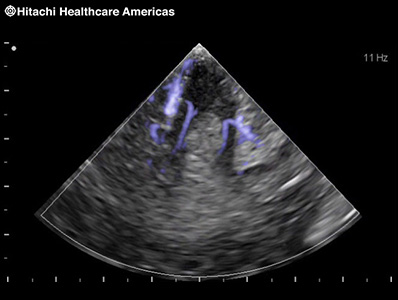

Directional eFLOW (D-eFLOW)

Displays blood flow with directional information at higher frame rates and spatial resolution compared to conventional methods. Detail and accuracy of blood flow information is greatly increased with reduced blooming of color.